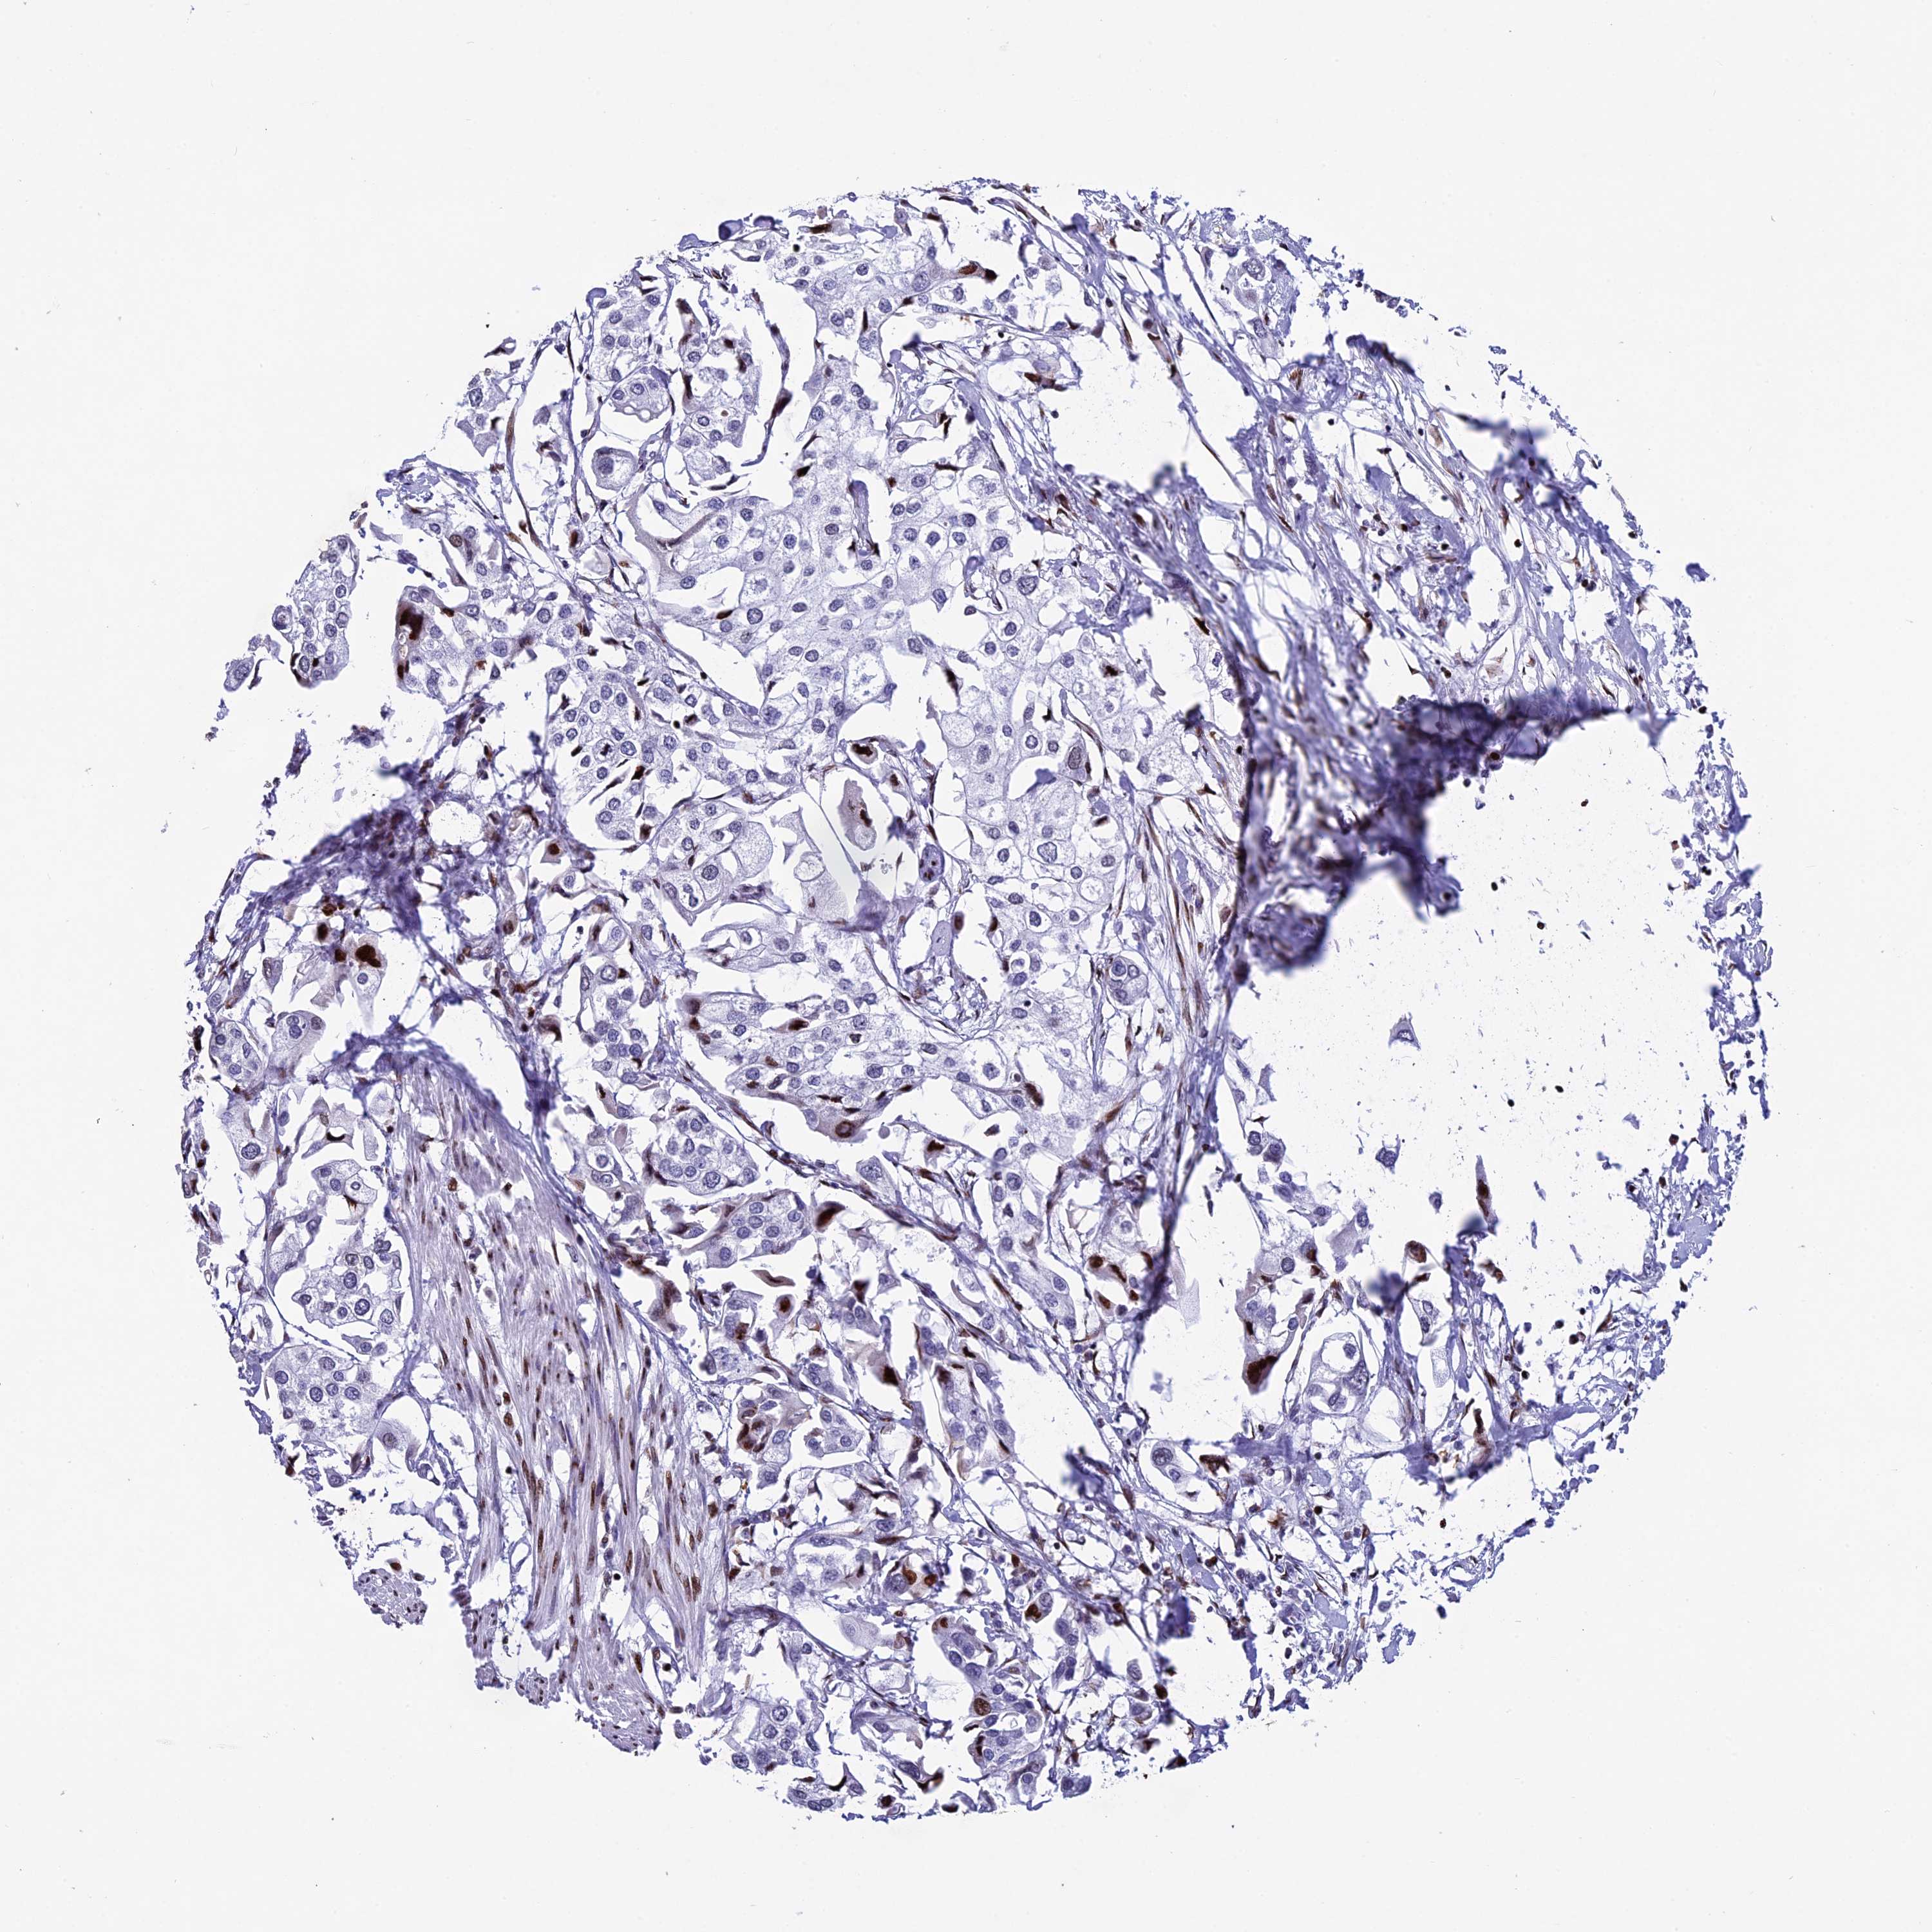

UROTHELIAL CANCER - Protein expressioni

A mouse-over function shows sample information and annotation data. Click on an image to view it in a full screen mode. Samples can be filtered based on level of antibody staining by selecting one or several of the following categories: high, medium, low and not detected. The assay and annotation is described here.

Note that samples used for immunohistochemistry by the Human Protein Atlas do not correspond to samples in the TCGA dataset.

Antibody stainingi

Antibody staining in the annotated cell types in the current human tissue is reported as not detected, low, medium, or high, based on conventional immunohistochemistry profiling in selected tissues. This score is based on the combination of the staining intensity and fraction of stained cells.

Each image is clickable and will lead to virtual microscopy that enables deeper exploration of all samples and also displays staining intensity scores, fraction scores and subcellular localization as well as patient and tissue information for each sample.

Antibody HPA041424

Antibody HPA042048

Urothelial carcinoma, High grade

Urothelial carcinoma, Low grade